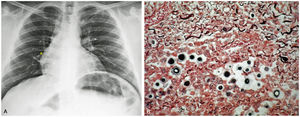

A 35-year-old male presented with a nine-month history of progressively worsening right hemithorax pain, dry cough, and occasional nocturnal diaphoresis. In the fifth month, his symptoms intensified, prompting hospitalization for community-acquired pneumonia, treated with a one-week course of antibiotics. Partial improvement was noted, but symptoms persisted. Physical examination revealed diminished breath sounds in the right lung base. A chest X-ray showed opacities in the perihilar and lower zones of the right lung, consistent with chronic infiltrates (Fig. 1A). Bronchoalveolar lavage via fiberoptic bronchoscopy revealed a predominance of neutrophils (87%), but tests for tuberculosis were negative. A transbronchial biopsy was performed, and the histopathological analysis demonstrated granulomas with extensive necrosis and vacuolated structures, which stained positively with Grocott and Gomori stains (Fig. 1B), confirming a diagnosis of pulmonary cryptococcosis by Cryptococcus neoformans. He was treated with oral fluconazole at 400 mg daily for six months, leading to significant clinical improvement.

A. Initial Chest X-ray: Nodular opacity in the perihilar region and right lung base (yellow asterisk). B. Several encapsulated yeast-like structures were observed (Gomori stain, 40x). (For interpretation of the references to color in this figure legend, the reader is referred to the web version of this article.)